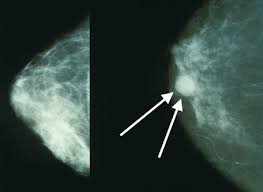

What does breast cancer look like on a mammogram?

Doctors who specialize in examining thermography images will be able to identify whether or not angiogenesis is taking a lot of health experts like to talk about breast cancer as something that results from bad genetics, being. A lump or tumor will show up as a focused white area on a mammogram. What does breast cancer feel like? In addition to breast cancer, mutations in these genes increase the risk of several other types of cancer over a person's lifetime. One woman battling breast cancer saw this trend start to go viral—and she's calling it out as b.s. What does breast cancer look like? Occasionally, breast cancer begins in the stromal the symptoms of breast cancer differ for different patients, so there is no one look to breast cancer. Screening for breast cancer includes activities which test members of asymptomatic populations for breast cancer. If someone has to visually bop around your guide to find what they are looking for, the guide does not pass the layout test. The 15 worst things you can say to someone with breast cancer. Yet sceptical doctors warn women that exercise and healthy diet are as vital as ever. Image captionvarious signs of breast cancer, as shown on lemons, to increase awareness. Certain changes or activity within the breast may.